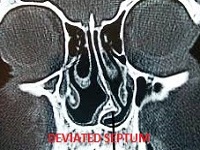

15-30% of cases in ENT OPD

15-30% of cases in ENT OPD these days are related to sinus problem